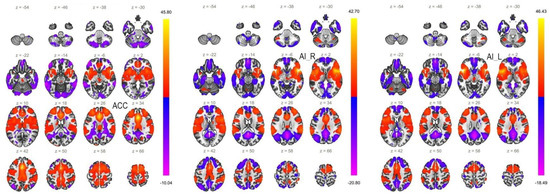

6.2. Functional Connectivity of the ACC Seed

6.3. Functional Connectivity of the AI Seeds

| Between-Group Contrast | MNI Coordinates x, y, z | Cluster Size | Cluster Threshold (p < 0.05, FWE) | Regions within the Cluster |

|---|---|---|---|---|

| P > HC | +32 −4 +46 | 697 | <0.001 | PostCG_R, PreCG_R, SPL_R |

| +2 −34 +52 | 526 | <0.001 | PostCG_R, SPL_R, PreCu, LOC_R—superior division, PostCG_L | |

| −24 −48 +52 | 106 | 0.017 | SPL_L | |

| HC > P | −10 −10 −24 | 109 | 0.015 | PHPG_L—anterior division, Brain stem |

| BD > HC | −02 −36 +66 | 1393 | <0.001 | PostCG_R, SPL_R, PostCG_L, PreCu |

| +24 −12 +66 | 120 | 0.009 | PreCG_R, SFG_R | |

| −2 −14 +44 | 105 | 0.018 | ACC, PCC, SMC_R | |

| +18 −72 +40 | 86 | 0.047 | LOC_R—superior division, PreCu, CC_R | |

| HC > BD | +24 −92 −28 | 138 | 0.004 | CerC1_R, CerC2_R |

| MDD > HC | +22 −56 +56 | 112 | 0.013 | SPL_R, LOC_R, superior division |

| MDD > BD | −46 −70 −32 | 191 | <0.001 | CerC1_L |

| Between-Group Contrast | MNI Coordinates x, y, z | Cluster Size | Cluster Threshold (p < 0.05, FWE) | Regions within the Clusters |

| P > HC | −8 −52 +64 | 201 | <0.001 | PostCG_L, PreCu |

| BD > HC | +54 −06 +18 | 108 | 0.017 | PostCG_R, PreCG_R |

| MDD > BD | −4 +12 +58 | 80 | 0.068 | SFG_L, SFG_R, SMC_R |